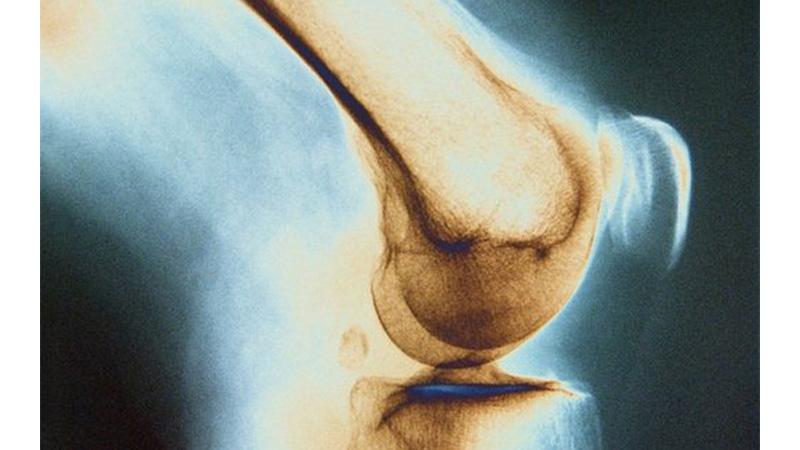

Для выявления туберкулеза костей используется рентгенологическое исследование как легких, так и пораженного участка скелета. На рентгеновских снимках можно четко увидеть такие изменения в костях, как сужение суставных щелей, неровные поверхности хрящей, размытые контуры поврежденных костей, образование полостей и расслоение межмышечных промежутков, вызванное отеком. Туберкулезный абсцесс отображается в виде тени рядом с очагом поражения.